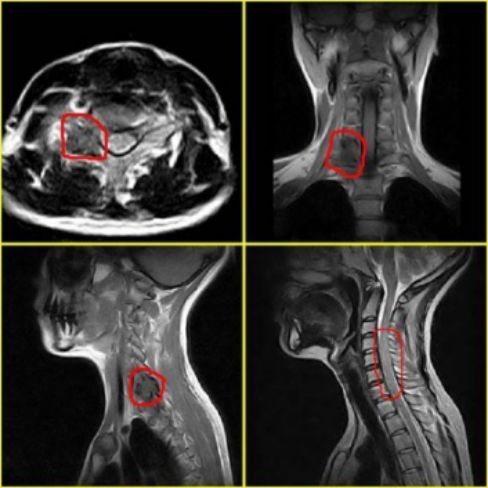

3、MRI:可显示骨折所致血肿及脊髓损伤所表现出的异常高信号。(平扫)

脊髓损伤定位诊断

【上颈髓损伤】上颈段主指颈椎1、2节段者,为便于表达,现将颈髓分为C1-4及C5-8上下两段。颈髓1-4之间受损时,病情多较危笃,且病死率高,约半数死于现场或搬运途中。其主要表现为: